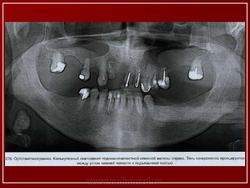

Стоматология. Калькулёзный сиалоденит. +

Калькулёзный сиалоденит.

Слюнокаменная болезнь

Сиалолитиаз

Конкременты слюнных желез